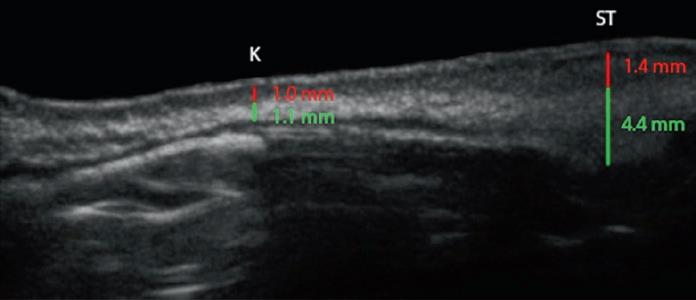

Sonogram analysis of the nasal skin is an extremely valuable tool, both for preop and postop analysis in rhinoplasty surgery. Patients found to have thin skin had a dermal thickness at the keystone junction (K) of 0.2 mm (0.1–0.4 mm), compared with 0.36 mm (0.28–0.40 mm) for normal skin and 0.48 mm (0.42–0.63 mm) for thick skin (Fig. 1.20) (Kosins and Obaghi 2017). This difference in thickness also existed in the supratip and tip areas, but these areas were also affected by the oiliness of the skin. Overall, patients with skin that was determined to be oily had a dermal thickness that was 25% thicker at the supratip and 34% thicker at the tip area. Soft tissue thickness underlying the dermis was variable. Patients of non-Caucasian background were more likely to have a thicker soft tissue layer. Patients with thick skin can be divided into those with thick dermis, thick underlying soft tissue, or both.

Fig. 1.20 Sonograms of nasal skin, showing the thickness of the dermis (red ) and SMAS ( green). (a, b) Thin skin. (c , d) Medium skin. (e, f ) Thick skin. K keystone junction; ST supratip; T tip (Sonograms courtesy of Aaron Kosins, MD.)